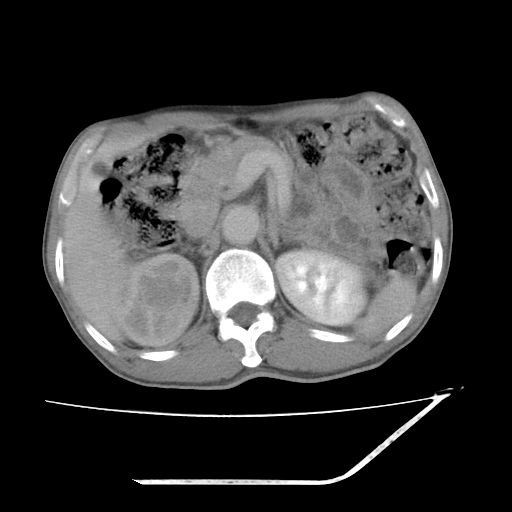

考虑右肾盂癌,肾动脉受侵,右肾功能减退,右肾盂输尿管积水,管壁增厚,考虑种植转移,应该把下面扫完的

支持右侧肾盂癌伴肾静脉瘤栓形成可能性大,右肾结石.肝右叶后段低密度影,不除外转移.

考虑右侧肾盂癌。右侧输尿管扩张未扫描完。

右肾盂旁ca并肾静脉瘤栓形成/肾功能降低。

右肾结石。

右肾盂癌,肾动脉受侵,右肾盂输尿管积水,管壁增厚,考虑种植转移

右肾盂移行细胞癌并右输尿管中段转移.肾积水.

1.右侧肾盂癌伴肾盂积水。

2.肾脏功能减退,原因有:(1)肾动脉受侵。(2)肾静脉受侵(3)肾积水,等。本例,肾动脉显影较好,但受压明显;肾静脉无明显显示,受压或静脉癌栓,下腔静脉腔内未见明显充盈缺损。

3.右侧上段输尿管扩张,原因:(1)积水所致;(2)种植。